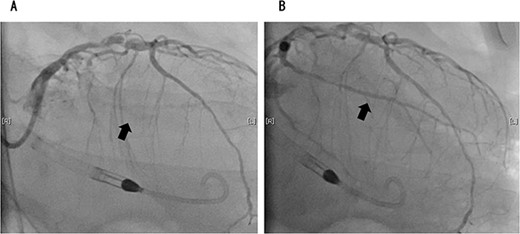

On the 2nd postoperative day, the patient experienced cardiac arrest because of a sudden drop in the saturation of percutaneous oxygen, after which his heartbeat resumed and he was intubated and placed on a ventilator. Transthoracic echocardiography showed left ventricular ejection fraction of 30%, diffuse hypokinesis of left ventricular wall motion and asynergy. Electrocardiography showed complete right bundle branch block, but no ST-segment elevation. Blood tests showed marked elevation of myocardial desensitization enzymes (CK: 362 U/L, cardiac troponin: 1143 pg/ml). Since ischemic heart disease could not be ruled out, angiography was performed. Coronary angiography revealed acute coronary syndrome with 90% occlusion of the left circumflex branch and 100% occlusion of the left anterior descending branch (Figs 3 and 4). The patient experienced shock and required VA-ECMO. However, the circulatory dynamics were unstable, and intra-aortic balloon pumping (IABP) was introduced. Furthermore, because the blood pressure could not be maintained with circulatory support from the IABP, we converted it to Impella 5.0. Assisted circulation with Impella 5.0 stabilized the patient’s blood pressure and allowed us to open the left circumflex and left anterior descending branches. VA-ECMO initially required an auxiliary flow of 1.2 L/min, which could be gradually reduced; Impella 5.0 initially required an auxiliary level of P7, which was reduced to P5 after VA-ECMO removal. VA-ECMO and Impella 5.0 were discontinued on the 6th and 8th postoperative days, respectively. He was eventually transferred by walking to a nearby facility for further rehabilitation 109 days later. One year later, the patient was recurrence-free of lung cancer.

Coronary angiography showed 90% occlusion of the left anterior descending branch (A). After the procedure, the occlusion was completely released (B).